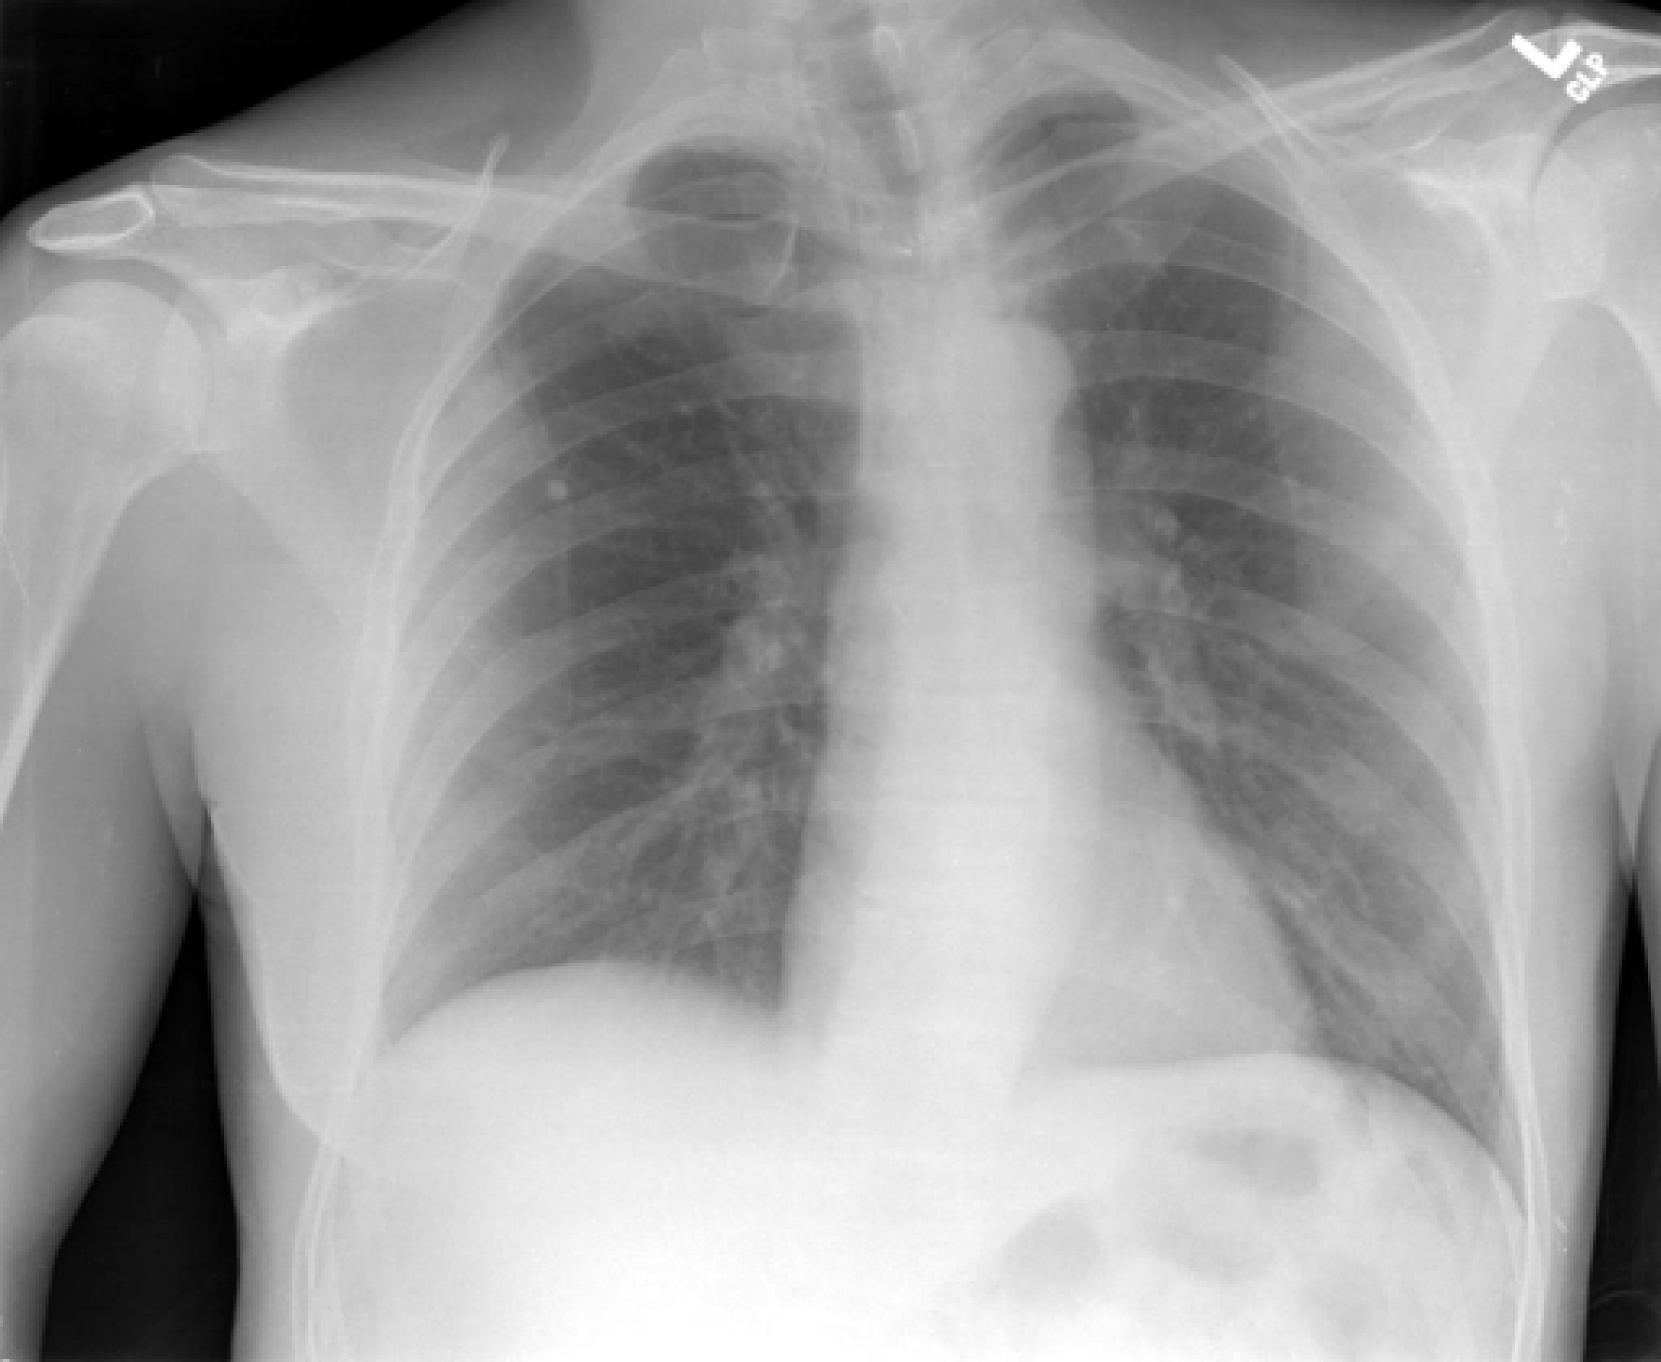

In the context of medical image analysis, radiology reports serve as a rich source of information. Radiologists routinely generate these free-text reports, which typically include sections such as comparison, indication, findings, and impression, as illustrated in Figure 1.

Refer to caption Comparison: Chest radiographs XXXX. Indication: XXXX-year-old male, chest pain. Findings: The cardiomediastinal silhouette is within normal limits for size and contour. The lungs are normally inflated without evidence of focal airspace disease, pleural effusion, or pneumothorax. Stable calcified granuloma within the right upper lung. No acute bone abnormality.

Impression: No acute cardiopulmonary process.

Figure 1: Example image and report from the IU X-ray dataset Demner-Fushman et al. (2015)

A crucial aspect in addressing such tasks is the accurate comprehension of factual information within the report. Specifically, the findings and impression sections can be considered as repositories of factual information regarding the imaging examination. These factual statements encompass various elements, including observations (such as abnormalities, diseases, or devices), interpretations derived from observations, references to anatomical locations, discussions on severity or confidence levels, comparisons to previous studies, and more. For instance, in Figure 1, one factual statement indicates no acute bone abnormality (a normal observation), while another describes a stable calcified granuloma within the right upper lung (an abnormality found in a specific anatomical site).